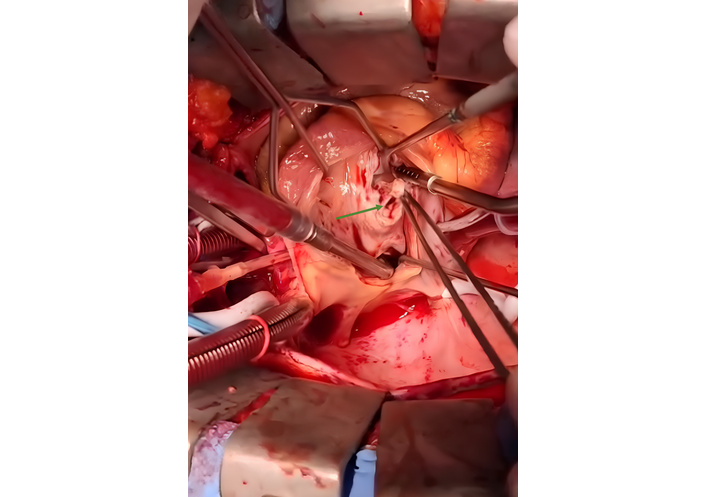

The defect was surgically repaired by thoracotomy, and a communication orifice of approximately 1.5 cm was visualized intraoperatively, below the septal cusp of the tricuspid valve, with this cusp divided in half (Figure 3). The septal defect was closed with a bovine pericardial patch (Figure 4), and the leaflet was reconstructed, without perioperative complications.

Intraoperative view of the Gerbode defect. A view from the left ventricle showing the communication between this chamber and the right atrium (green arrow).